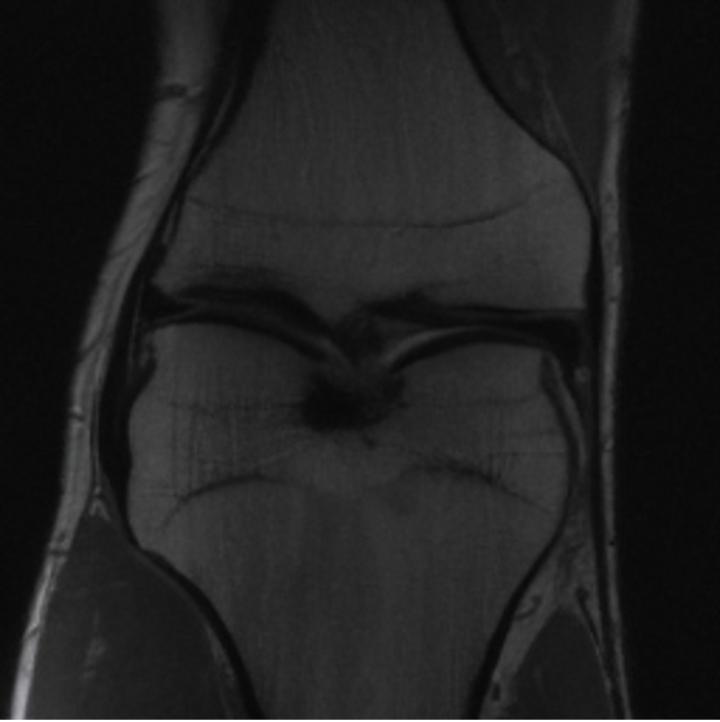

One way to test the generalization capability of the trained X-Diffusion is to test it on a completely different domain from an MRI dataset not seen during training. We report the single-slice results on the test set of knees from NYU fastMRI [33, 80], using the X-Diffusion trained on the BRATS brain MRIs. The test PSNR result is 34.17 and an example is shown in Figure 8. It shows how successfully X-Diffusion can generate knee MRIs (out-of-domain) despite being trained on brains.

Small Knee MRIs clinical study. To qualitatively assess how realistic our generated knee out-of-domain 3D volumes were (produced from a single slice), we gave 20 generated examples alongside their real MRI counterparts to an expert orthopedic surgeon J. F.. He was then asked to identify the real example from a set of 20 MRI pairs. The surgeon correctly identified the real MRI in only 10 out of 20 pairs, could not decide in 3 pairs, and misidentified the generated MRI as real in the remaining 7 pairs. This further validates the generated out-of-domain MRIs.